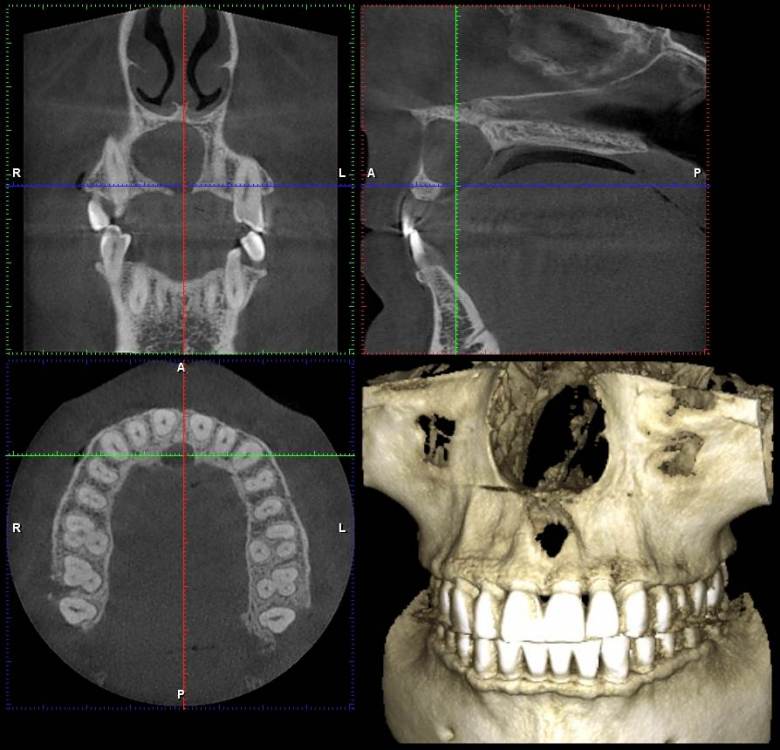

NazranDantist Опубликовано 3 декабря, 2021 Поделиться Опубликовано 3 декабря, 2021 Всем привет. Коллеги, вот такая ситуация обнаружилась на снимке. Со слов пациента, ничего не беспокоит, зубы интактные, травмы не было,холодовая проба положительная. Какую тактику лечения выбрать? Ну и в чем причина? Ссылка на комментарий

Irouil Опубликовано 3 декабря, 2021 Поделиться Опубликовано 3 декабря, 2021 Похоже на кисту резцового канала я бы пошёл на декомпрессию, потом удалил 4 3 Ссылка на комментарий

NazranDantist Опубликовано 4 декабря, 2021 Автор Поделиться Опубликовано 4 декабря, 2021 (изменено) 15 часов назад, Irouil сказал: Похоже на кисту резцового канала я бы пошёл на декомпрессию, потом удалил Спасибо. Как считаете, доступ небный делать? Или вестибулярной тоже зайти? Изменено 4 декабря, 2021 пользователем NazranDantist Ссылка на комментарий

Irouil Опубликовано 4 декабря, 2021 Поделиться Опубликовано 4 декабря, 2021 39 минут назад, NazranDantist сказал: Спасибо. Как считаете, доступ небный делать? Или вестибулярной тоже зайти? Основной у Вас будет все равно небный, а если встретите сложности с диссекцией в области вестибулярной узуры (что навряд) - добавите второй. Ссылка на комментарий